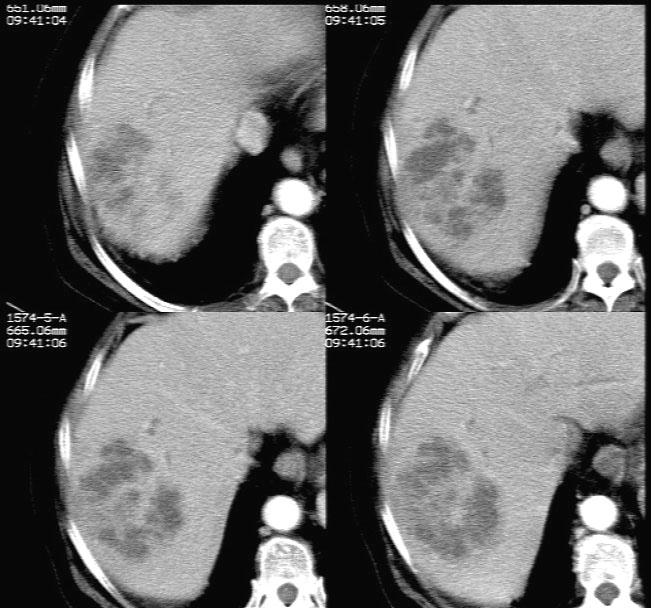

ct增强扫描示: 动脉期肝右后叶团状低密度边缘明显不均性强化,内呈不规则峰窝状低密度(无强化区),不规则分隔亦见明显强化;三期扫描像均见,病灶有明显占位征,周围血管、胆管推挤外移,病灶与正常肝组织分界不清,延迟期病灶周围见雾状略低密度(较肝左叶)。

肝右后叶团状低密度占位性病变,结合临床提示: 1、肝脓肿? 2、不排除肝ca可能。建议afp检查。

病灶三期明显强化,强化后边缘清楚,病灶内侧部分层面可见分层改变,支持考虑肝脓肿

平扫示肝右后叶见团状低密度灶,边界欠清,密度略不均匀,ct值28-32hu,肝内胆管无扩张。ct增强扫描动脉期肝右后叶团状低密度边缘明显不均性强化,内见多发斑片状无强化液化区,呈不规则峰窝状。

考虑肝脓肿早期(蜂窝组织炎阶段)。

鉴别:肝血管瘤,早期周边强化明显,逐渐向中心充填。原发性肝癌,强化一般呈快进快出,多有乙肝肝硬化病史。